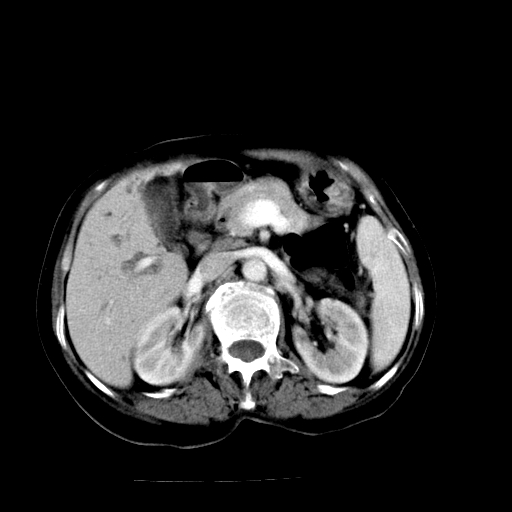

以下是引用随光逐影在2009-4-7 8:21:00的发言:[br]肝内外胆管多发性结石并肝内外胆管扩张;胆系感染。